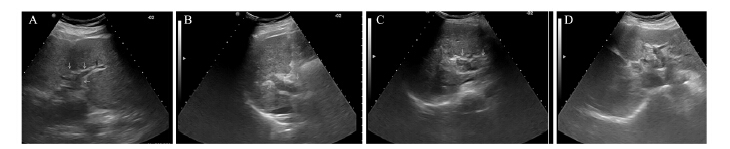

所有患者均按治疗计划顺利完成治疗。通过 超声和增强CT,观察瘤栓的分布范围、大小和 门静脉血流的变化。A组的近期有效率70.59% (24/34),B组的近期有效率67.74%(21/31), 两组疗效比较差异没有统计学意义(χ2=0.062, P=0.804),见表 2、图 2~3。

|

| A: left branch of PVTT before 3-DCRT; B: the tumor thrombosis disappeared after 3-DCRT; C: color Doppler rheography after 3-DCRT 图 3 Ⅰ级癌栓三维适形放疗前后声像图 Figure 3 Contrast image of grade Ⅰ PVTT before and after 3-DCRT 表 3 |